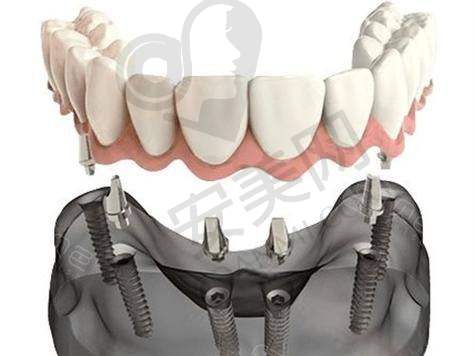

all - on - 4 半口种植牙是一种精良的牙齿种植技术。它通过在牙槽骨内植入四颗种植体,然后利用这四颗种植体来支撑半口牙桥,从而实现半口牙齿的修复。与传统的种植牙技术相比,all - on - 4 半口种植牙具有许多优势。

首先,手术时间短。传统的半口种植牙可能需要植入更多的种植体,手术过程复杂,时间较长。而 all - on - 4 半口种植牙只需要植入四颗种植体,大大缩短了手术时间,减少了患者的痛苦。其次,费用相对较低。由于减少了种植体的使用数量,all - on - 4 半口种植牙的费用相对传统种植牙更为亲民。末尾,稳定性好。四颗种植体呈特定的角度植入牙槽骨内,能够提供足够的支撑力,使牙桥更加稳定,咀嚼功能也能得到良好的修复。

此外,all - on - 4 半口种植牙还具有美观自然的成效。种植后的牙齿与天然牙齿非常相似,几乎看不出是人工种植的。而且,它的使用寿命也比较长,只要患者做好日常的口腔护理,就可以长期使用。